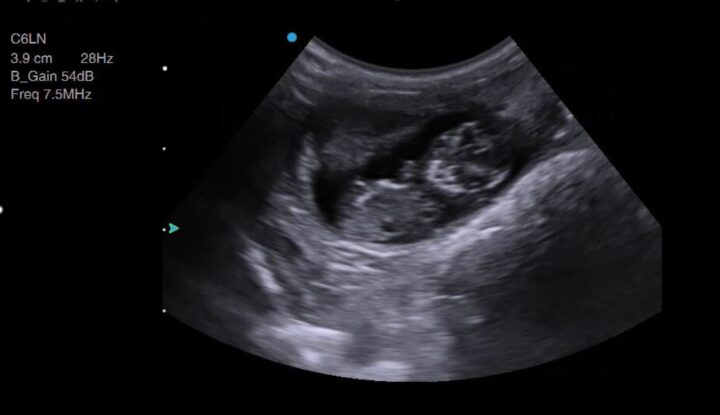

Manipulating your imaging plane is essential for certain measurements, such as crown–rump length and biparietal diameter. Still images can be ambiguous – Figure 3, for example, is not pregnancy – so watching a video clip (Video 1) instead makes this image more interpretable.